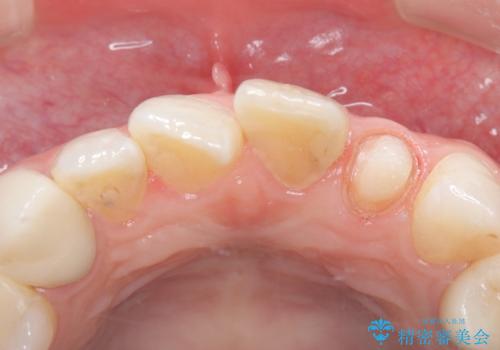

左上2番の唇側歯頚部が欠けており、根管治療を受けている歯でした。

レントゲン写真撮影を行ったところ、歯の中の土台が外れ欠けている状態でしたので土台と被せものの治療を行うこととしました。

外れ欠けている土台をまずやり替えた後、根管治療後の緊密な封鎖を目的としオールセラミッククラウンをセットしました。